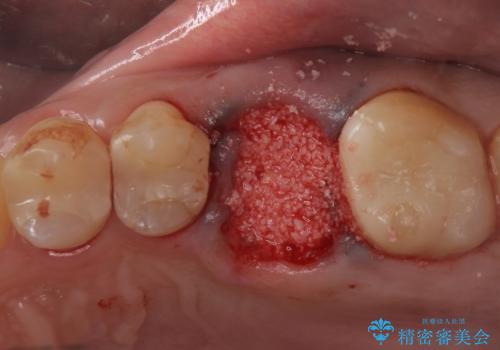

抜歯を行い、周囲の骨を増やしつつインプラントを埋入することとなりました。

- 左上6:歯槽堤保存術/110,000円 サイナスリフト/110,000円 骨造成/55,000円 静脈内鎮静/55,000円 インプラント体/242,000円 チタンカスタムアバットメント/110,000円 仮歯/22,000円 ジルコニアクラウン/121,000円 合計825,000円 左上5:セラミックインレー/77,000円費用は治療当時の料金となります

良い位置に良い方向でインプラントを埋入することができました。